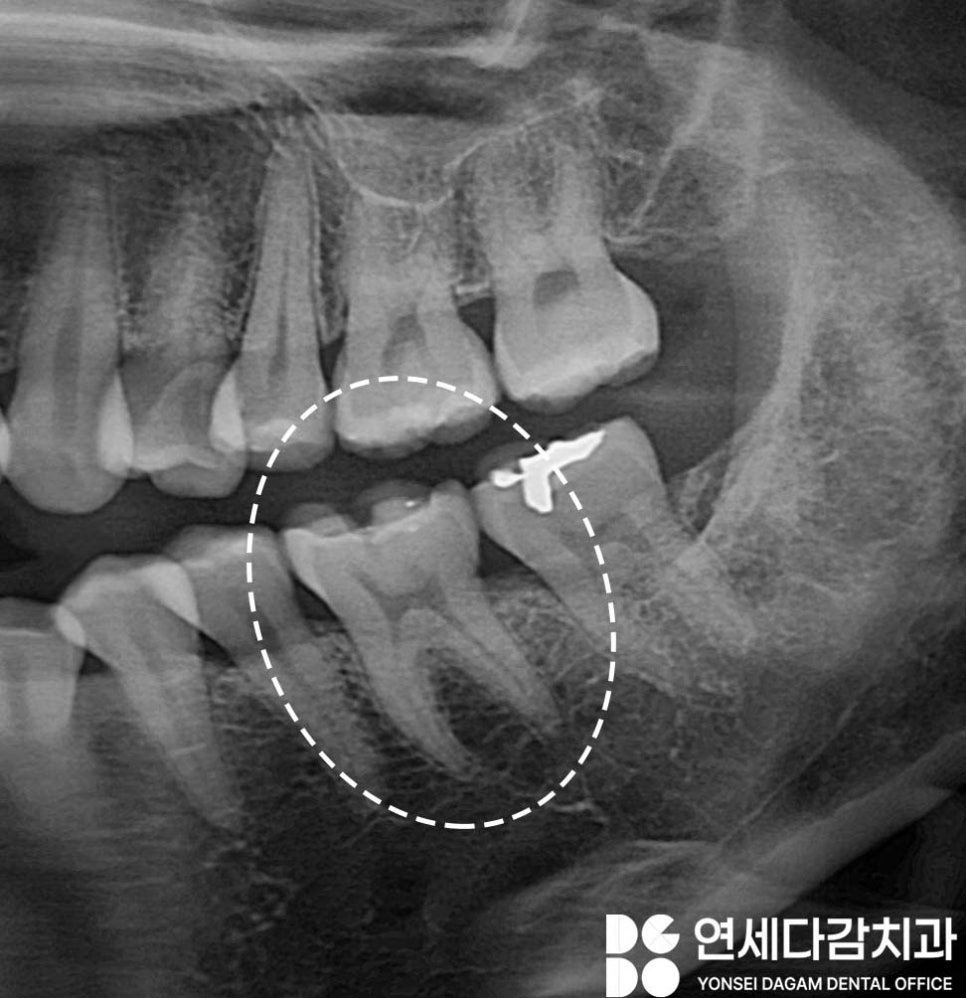

✔️ 예를 들어 오래된 인레이 주변에

2차 우식이 생겨서 인레이

지지가 약해지면서 발생하는 경우입니다.

인레이와 치아 사이에는

미세한 경계가 생기면

그 틈새로 세균이 들어가

감염을 발생시킬 수 있습니다.

따라서 오금역 치과 에서는

엑스레이를 통해 충치의 깊이를

살펴보는 과정도 중요시 여깁니다.

충치가 진행되면 치아 구조가

약해져 크라운 치료가 필요할 수 있습니다.